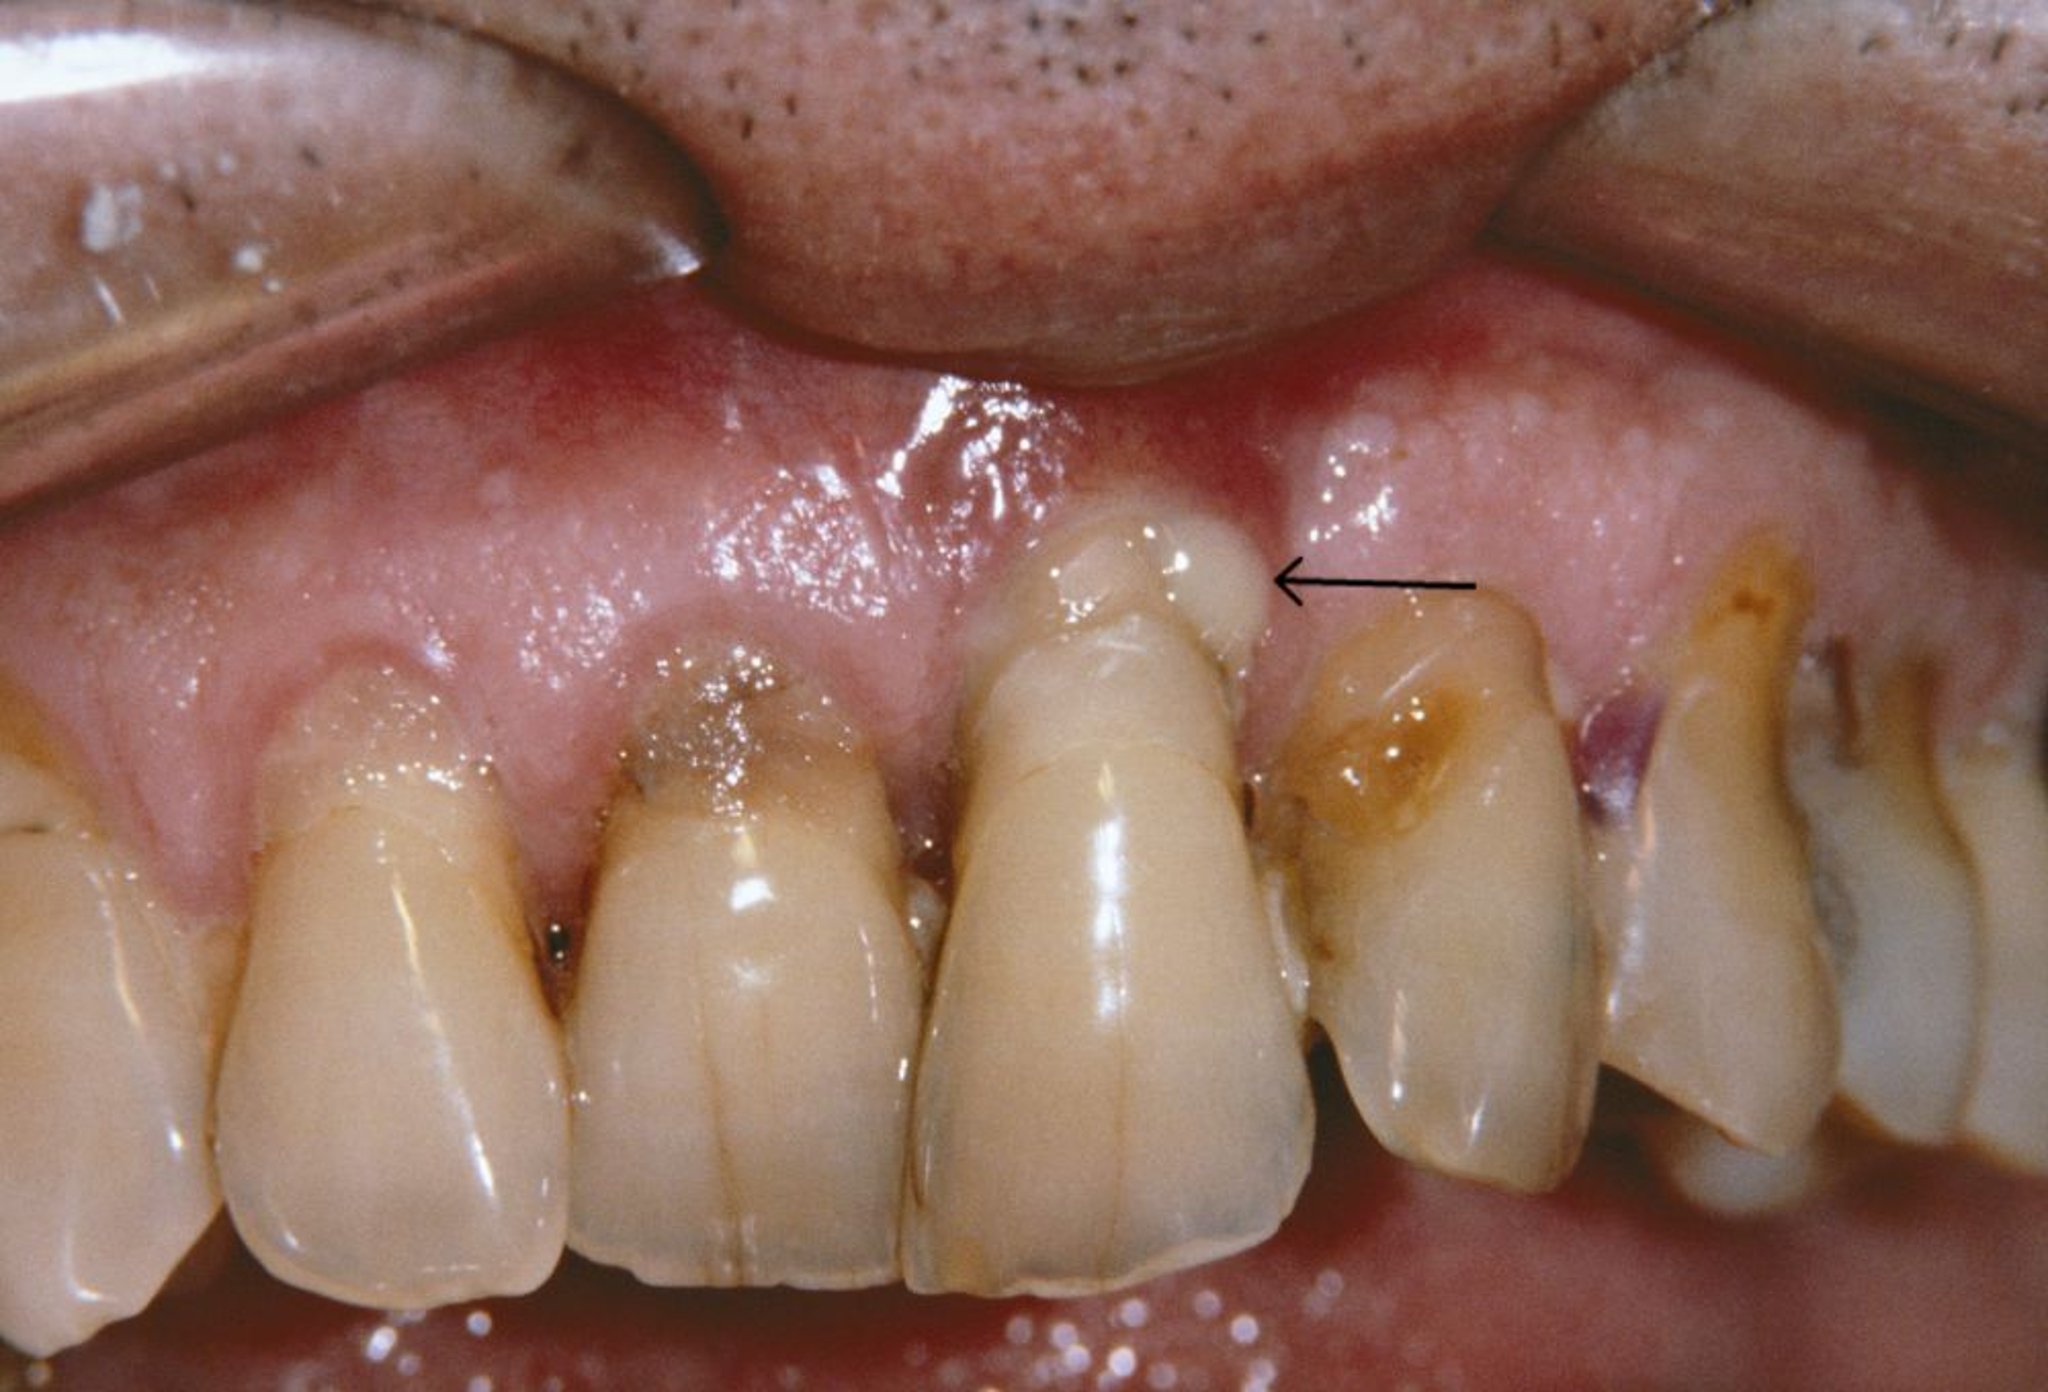

На этом фото показана рецессия десен и пародонтальный абсцесс (стрелка) у пациента с пародонтитом.